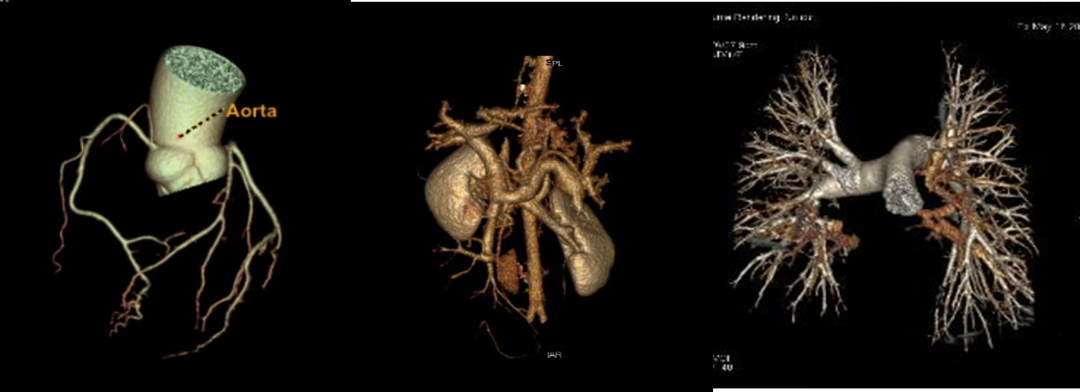

掃描速度快,全身檢查只需10秒鐘;對(duì)于血管性疾病,可發(fā)現(xiàn)更細(xì)小的血管分支;不受心率、呼吸限制,一次心跳即可完成冠脈CT檢查;噪音極小;單能量成像,更加準(zhǔn)確的絕對(duì)CT值;低KeV成像,更高的組織對(duì)比度;多參數(shù)功能成像,可進(jìn)行多種基物質(zhì)濃度及有效原子序數(shù)測(cè)定。

1.單能量圖像:能譜CT可提高圖像質(zhì)量,顯示病灶內(nèi)部特征,臨床可用于所有血管檢查及增強(qiáng)掃描。

2.物質(zhì)定量和分離:實(shí)現(xiàn)定量分析,臨床中常用的碘基物質(zhì)圖像可評(píng)估血管及強(qiáng)化程度。